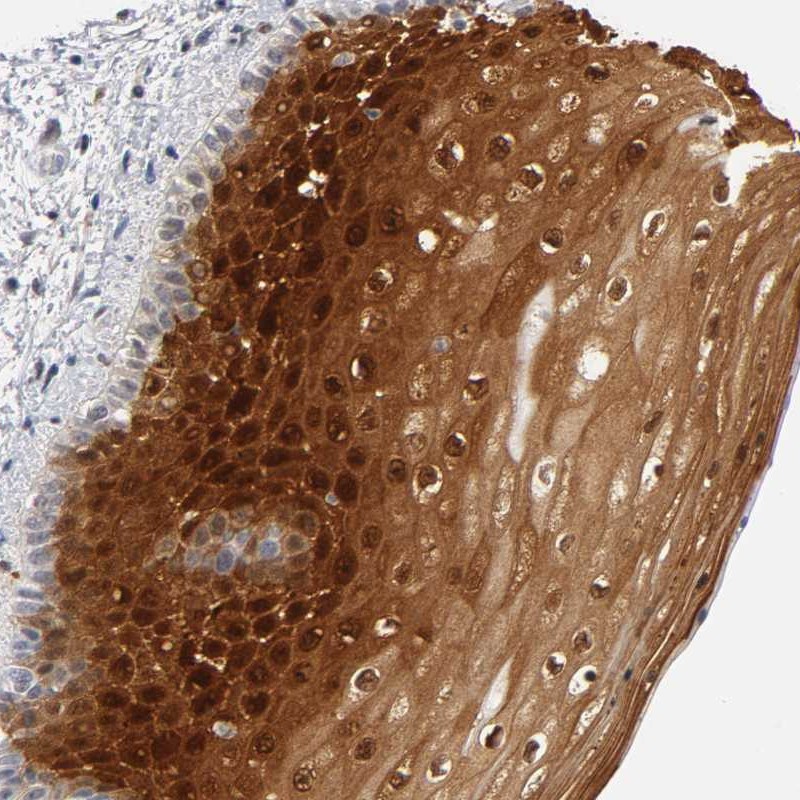

Immunohistochemical staining of human vulva/anal skin shows strong nuclear and cytoplasmic positivity in squamous epithelial cells.